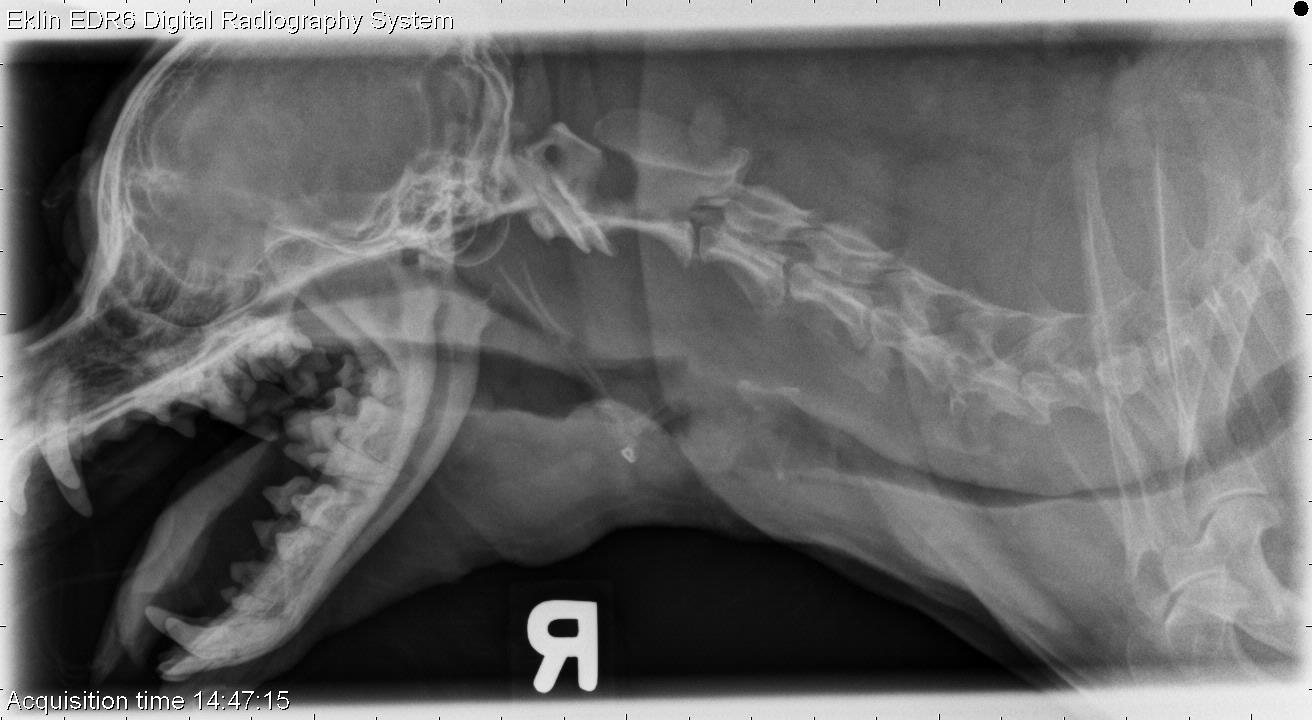

From www.veterinaryradiology.net

9 year old Yorkshire Terrier Elongation X Ray With elongation, the image appears stretched out of shape when. With elongation the apices of the teeth are often not seen radiographically. Elongation, an angulation that is too small or shallow. Elongation can also occur if the central ray is perpendicular to the object but the object is not parallel to the image receptor. This results in elongation, with the. Elongation X Ray.